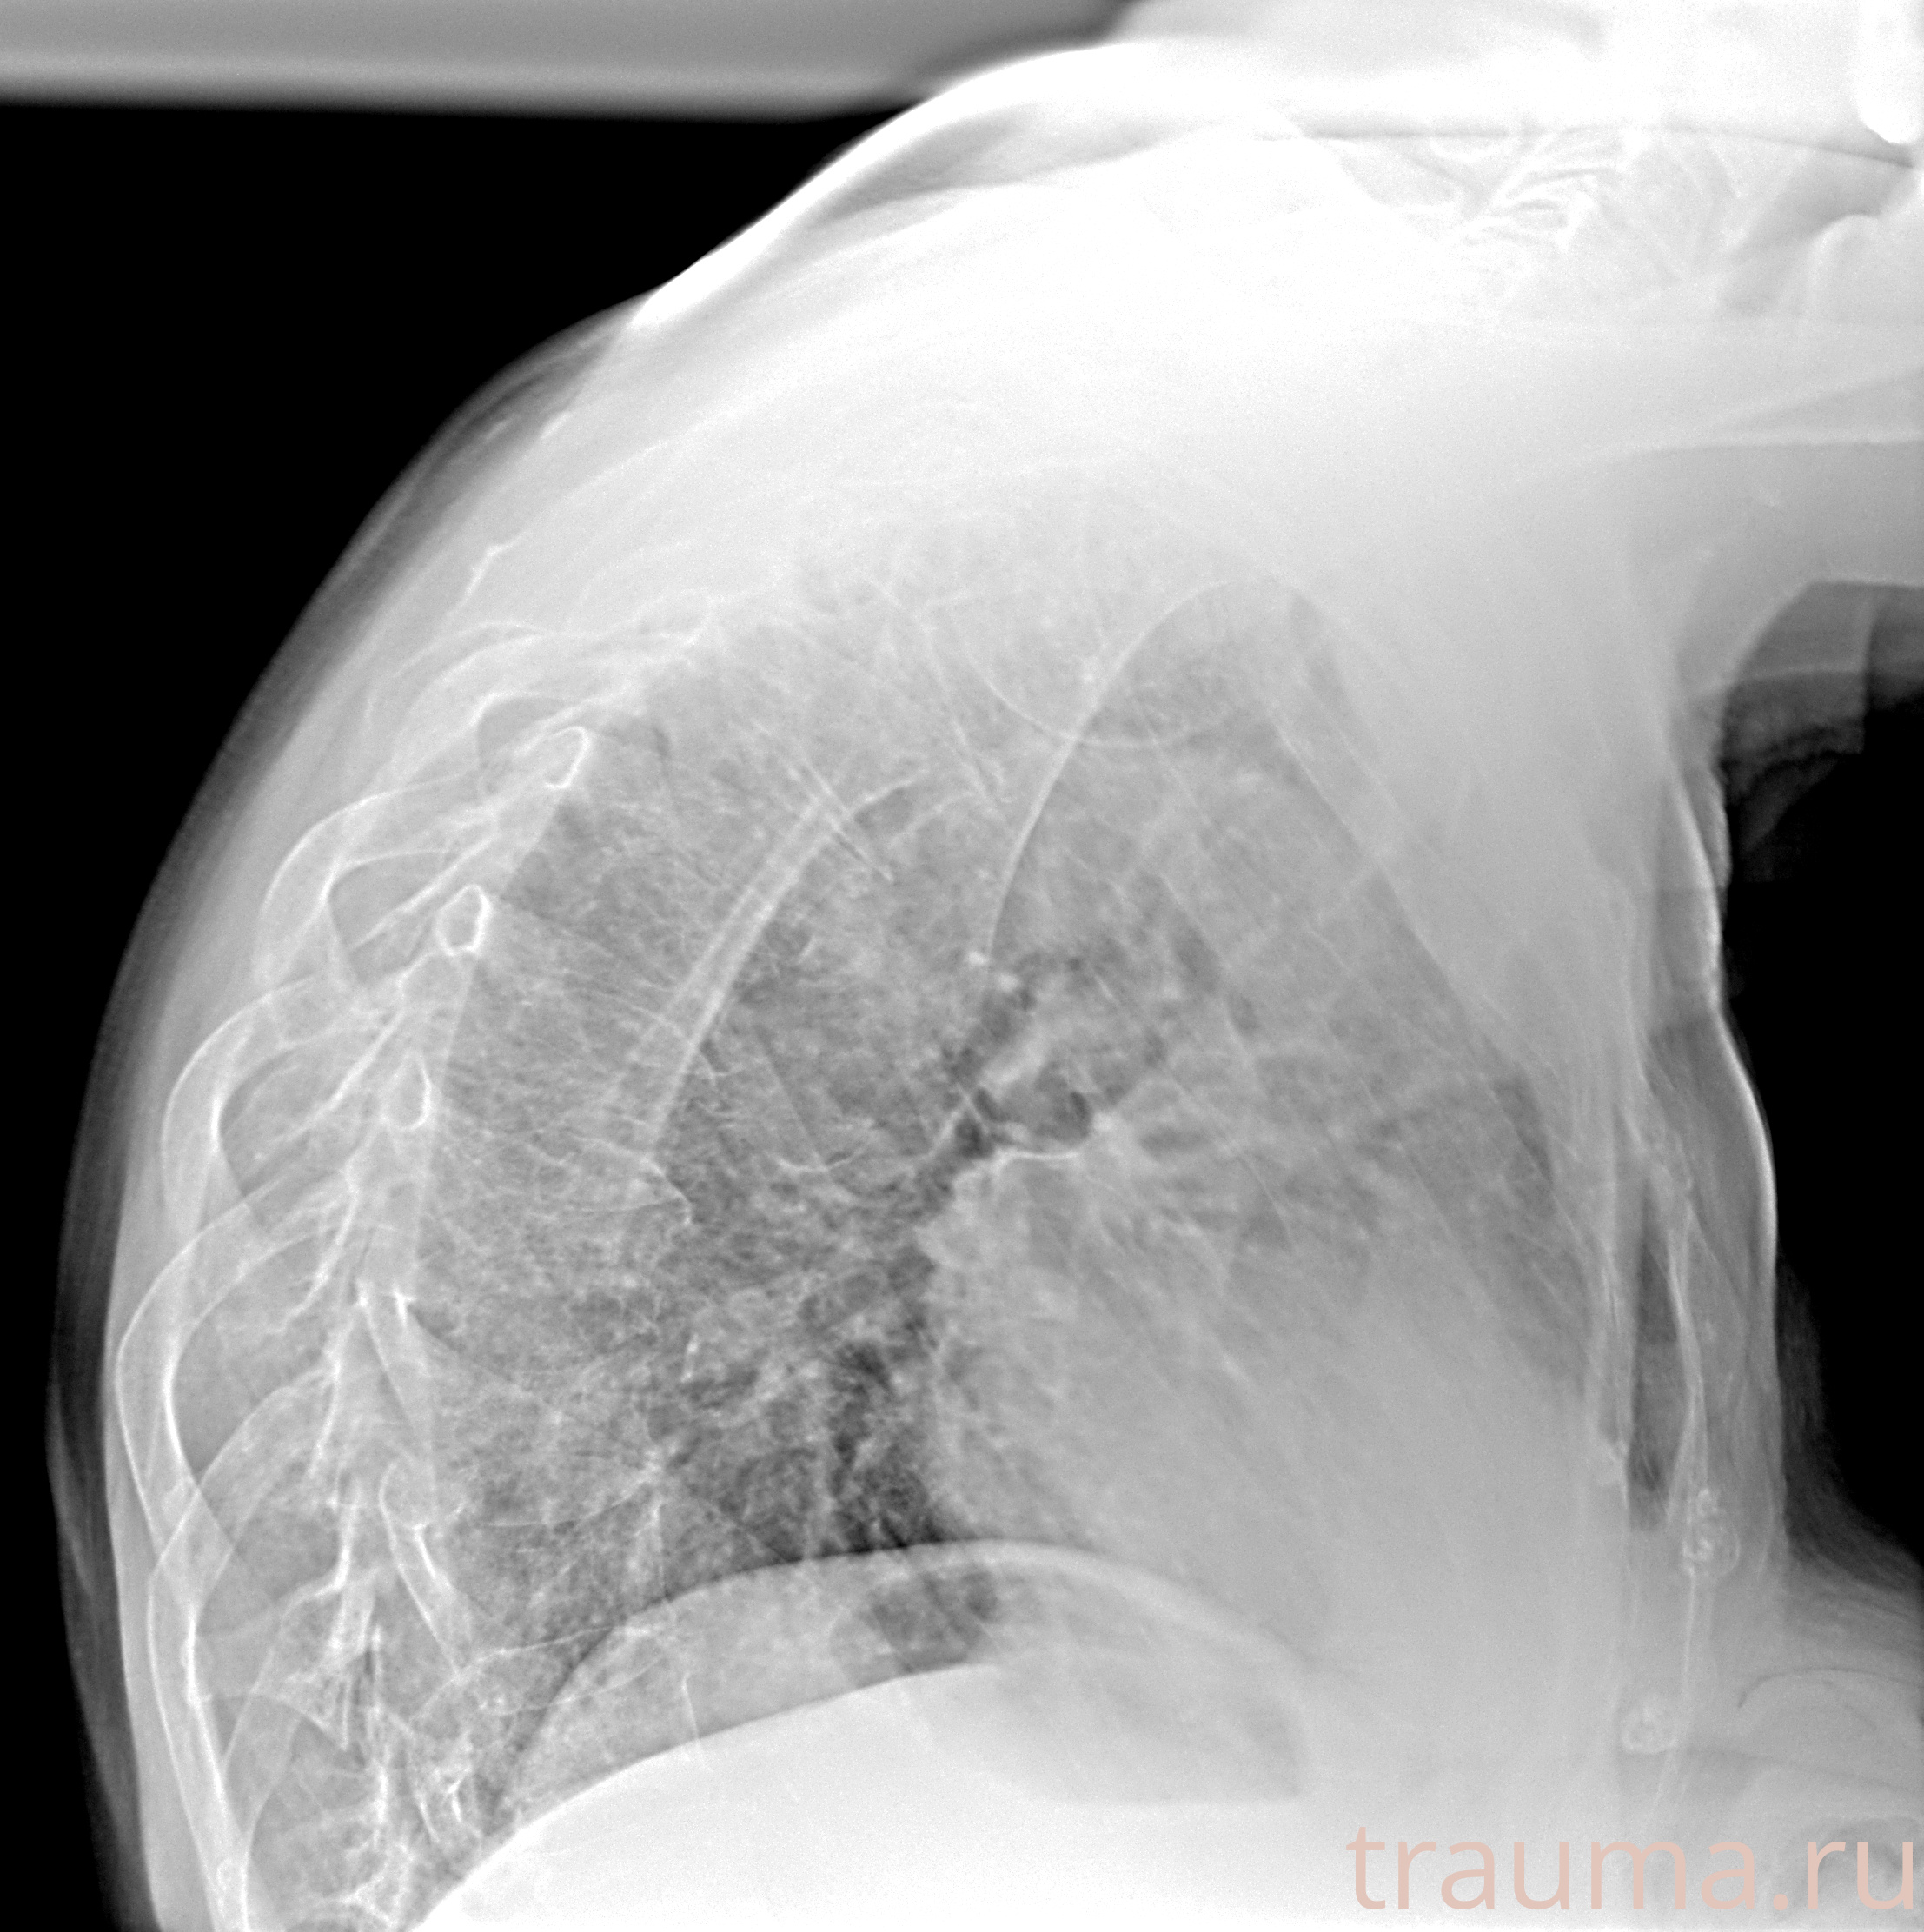

Рентгенограммы

Рентген на дому: по вашему адресу приезжает врач-рентгенолог, травматолог-ортопед с мобильным рентгеновским аппаратом, проводит диагностику травмы или заболевания, делает необходимые рентгенограммы, дает рекомендации по дальнейшему лечению. Получить качественные снимки в домашних условиях возможно благодаря уникальной методике, разработанной МосРентген Центром для института  Склифосовского